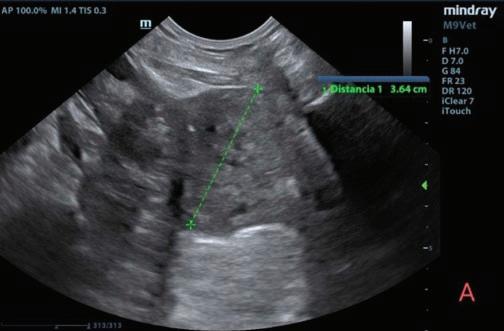

Se realizaron radiografías torácicas y en la proyección lateral derecha se observó, craneal a la silueta cardiaca, una opacidad tejido blando mal definida que producía efecto silueta positivo con esta. La tráquea se visualizó desplazada dorsalmente y el atrio izquierdo aumentado de tamaño. El parénquima pulmonar mostraba un aumento de opacidad en su área caudodorsal, compatible con un patrón pulmonar intersticial no estructurado difuso, el cual se consideró normal debido a que la radiografía fue tomada en fase espiratoria inicial

163

y a la condición corporal del paciente. En la proyección ventrodorsal, el mediastino craneal se observó en el límite superior de tamaño, presentándose un tamaño dos veces superior a la anchura de la vértebra torácica (Fig. 1). Este cambio es compatible con una imagen artefactual secundaria a la leve rotación que presenta la radiografía y a la condición corporal del paciente. El diagnóstico radiológico más probable fue una masa mediastínica craneoventral y cardiomegalia izquierda. En la ecocardiografía transtorácica se confirmó el diagnóstico de enfermedad degenerativa de la válvula

Figura 1. Radiografías torácicas en proyección lateral derecha (A) y ventrodorsal (B) donde se visualiza el área de opacidad de tejido blando craneal a la silueta cardíaca (flechas blancas). En la proyección ventrodorsal se visualiza el mediastino craneal que se presenta en el límite superior de grosor (flechas rojas).